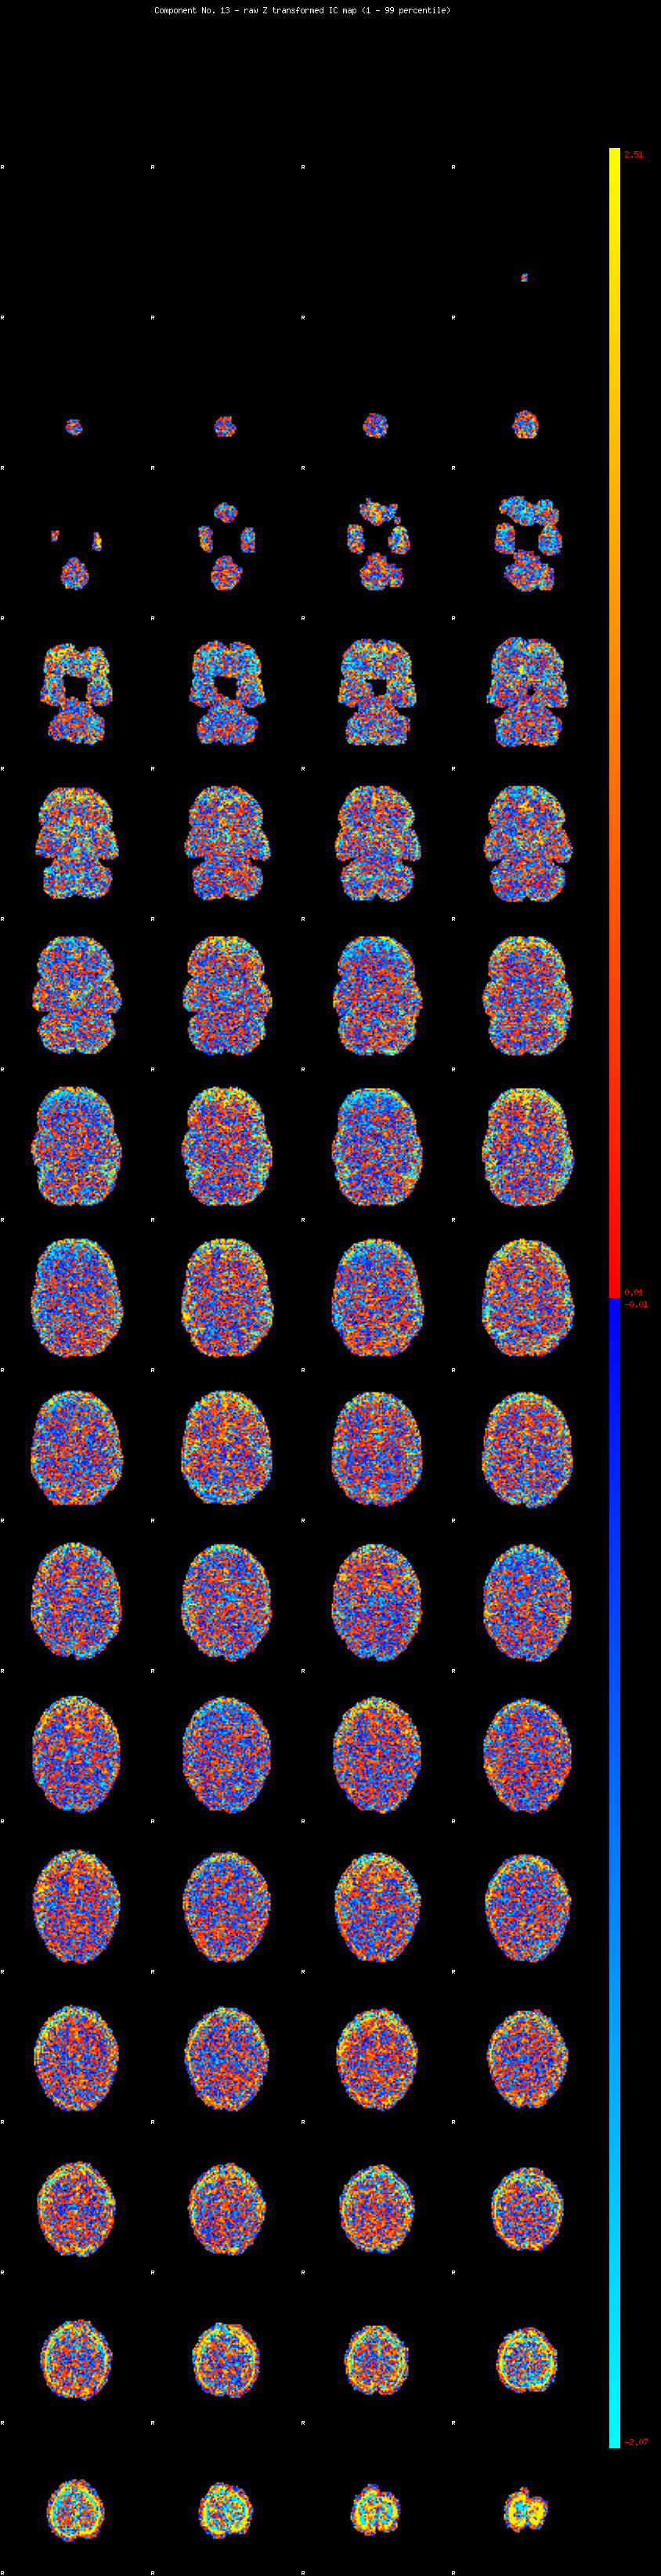

IC_13 Mixture Model fit

Means : -0.000000 2.924462 -2.549399

Vars : 1.000000 3.427930 1.383626

Prop. : 0.891974 0.069727 0.038298